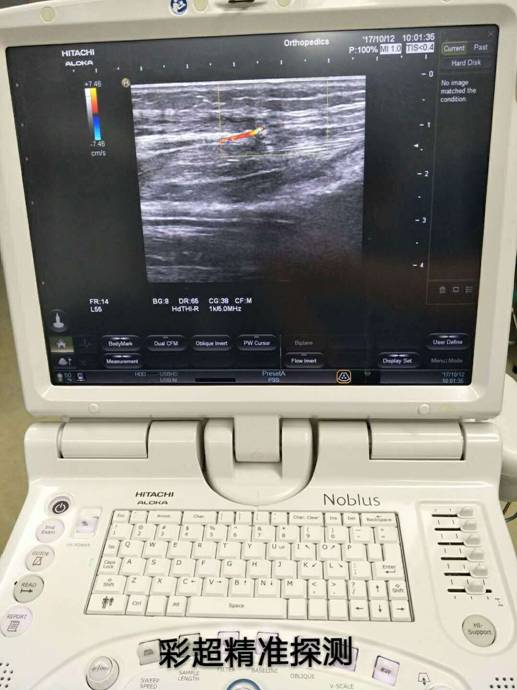

衡陽市中心醫(yī)院彩超定位精準治療骨折修復皮瓣

通訊員萬忠波 平國報道 粉碎性骨折+皮膚軟組織缺損+骨(肌腱)外露等損傷有了新療法,衡陽市中心醫(yī)院采用彩超精準定位、多學科協(xié)作施術,實現(xiàn)“大手術小創(chuàng)傷”。

骨科根據(jù)患者骨折情況分別施行骨折復位+內(nèi)(外)固定術,然后由燒傷整形科根據(jù)患者皮膚軟組織缺損情況,制定小腿穿支皮瓣轉(zhuǎn)移修復創(chuàng)面方案。為保證手術成功率,燒傷整形科會同超聲科由黃道遠主任于術前利用彩超精準的探測小腿術區(qū)的各個動脈穿刺,并逐一標記,再由燒傷整形科手術團隊根據(jù)動脈穿支的分布情況設計皮瓣,施行小腿穿支皮瓣轉(zhuǎn)移修復術。

由于采用了彩超定位技術,使得皮瓣設計方案更合理,手術操作更精準,手術耗時更少,更因為保護好了血管,術后皮瓣腫脹,存活均較以往有明顯改善,手術效果得到極大保障,患者滿意度大大提高。